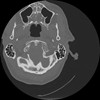

7 HUESO,,Vol,0.5,HUESO,,